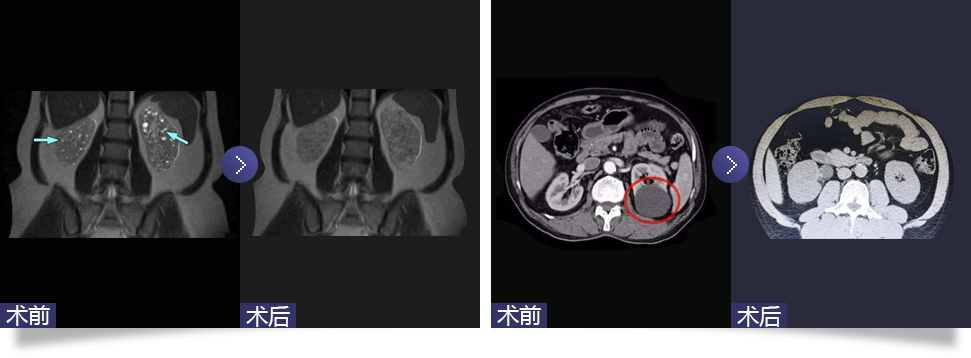

腹腔鏡下腎囊腫去頂減壓術(shù)

Laparoscopic renal cyst deparization and decompression

隨著腹腔鏡技術(shù)在泌尿外科領(lǐng)域的廣泛應(yīng)用,腹腔鏡下囊腫去頂減壓術(shù)成為治療腎囊腫的主要方法。通過腹腔鏡下用超聲刀切開腹膜,傷口為1.5-2.0cm,分離腎周脂肪,找到充分暴露的腎囊腫壁邊緣,切開囊腫壁并吸凈囊液。